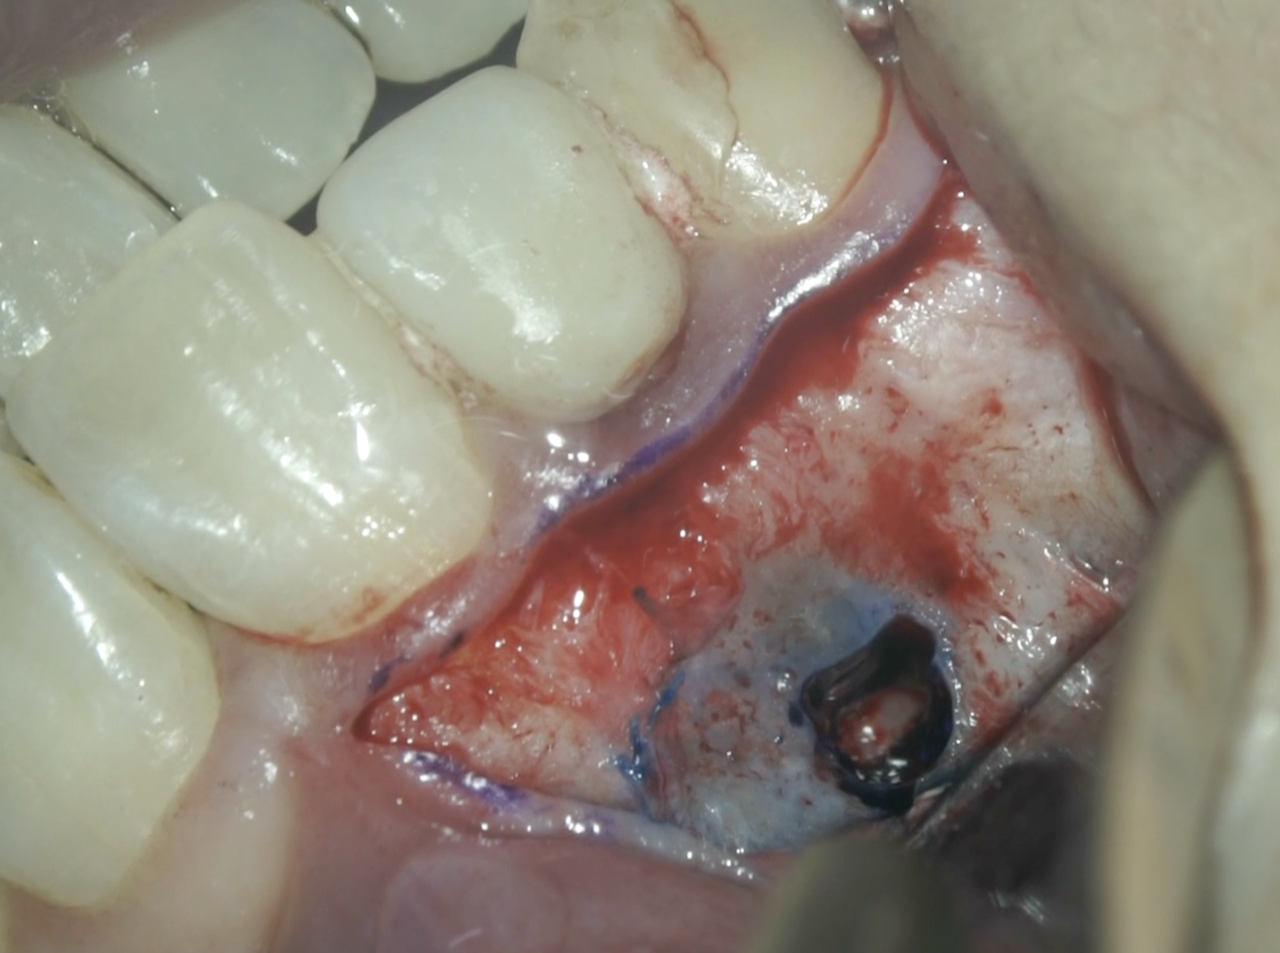

#7 Apicoectomy(2025.10.21)

Apexの位置はクラウンマージン部より12.5mm下方だ。

Apexと思しき部位をOsteotomyしApexを触知した。

Apex-3mmで根切した。

掻爬しメチレンブルーで染色した。

この白い物質は何だろうか?

臭いもない。

ユージノールなのだろうか?

私には何とも言えない。

さてもう一つ。

切断面があなたには見えるだろうか?

これを調整すると、

切断面が見える。